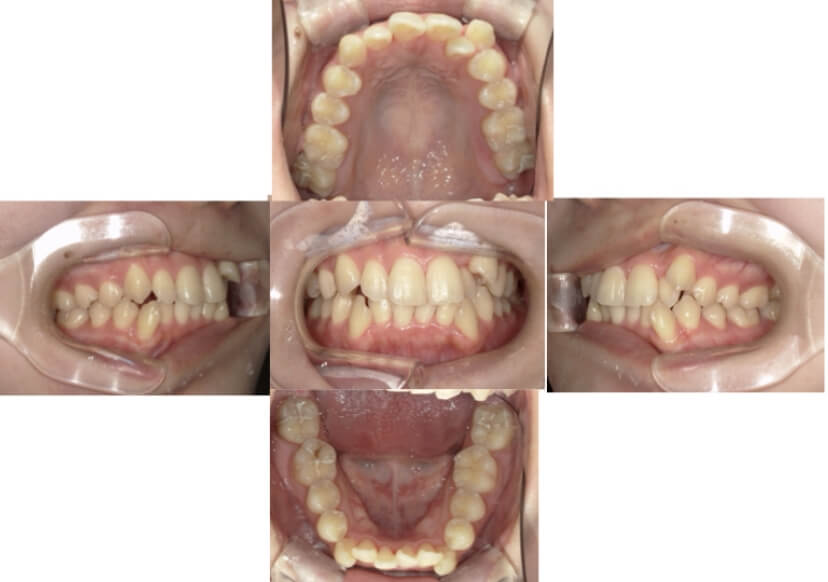

症例2

上下顎前突、叢生

抜歯

ブラケット矯正

上下顎前突、叢生(上下出っ歯、上下の前歯のガタガタ)のケースです。

装置はラビアル(上下表側)で、上下顎の小臼歯を4本抜歯を行っています。抜歯したスペースを使って、上下の前歯の後方移動と叢生(ガタガタ)の改善を行っています。

主訴 前歯のガタガタと口元がでているのが気になる。

年齢・性別 30歳 女性

お住まいの地域 東京都大田区

治療方針 抜歯スペースを利用して上前歯の叢生(ガタガタ)と口元突出の改善

抜歯部位 上下顎左右第一小臼歯

使用装置 ラビアル(上下表側)、顎間ゴム

治療期間 1年11か月

治療回数 13回

リテーナー クリアリテーナー

BEFORE

AFTER